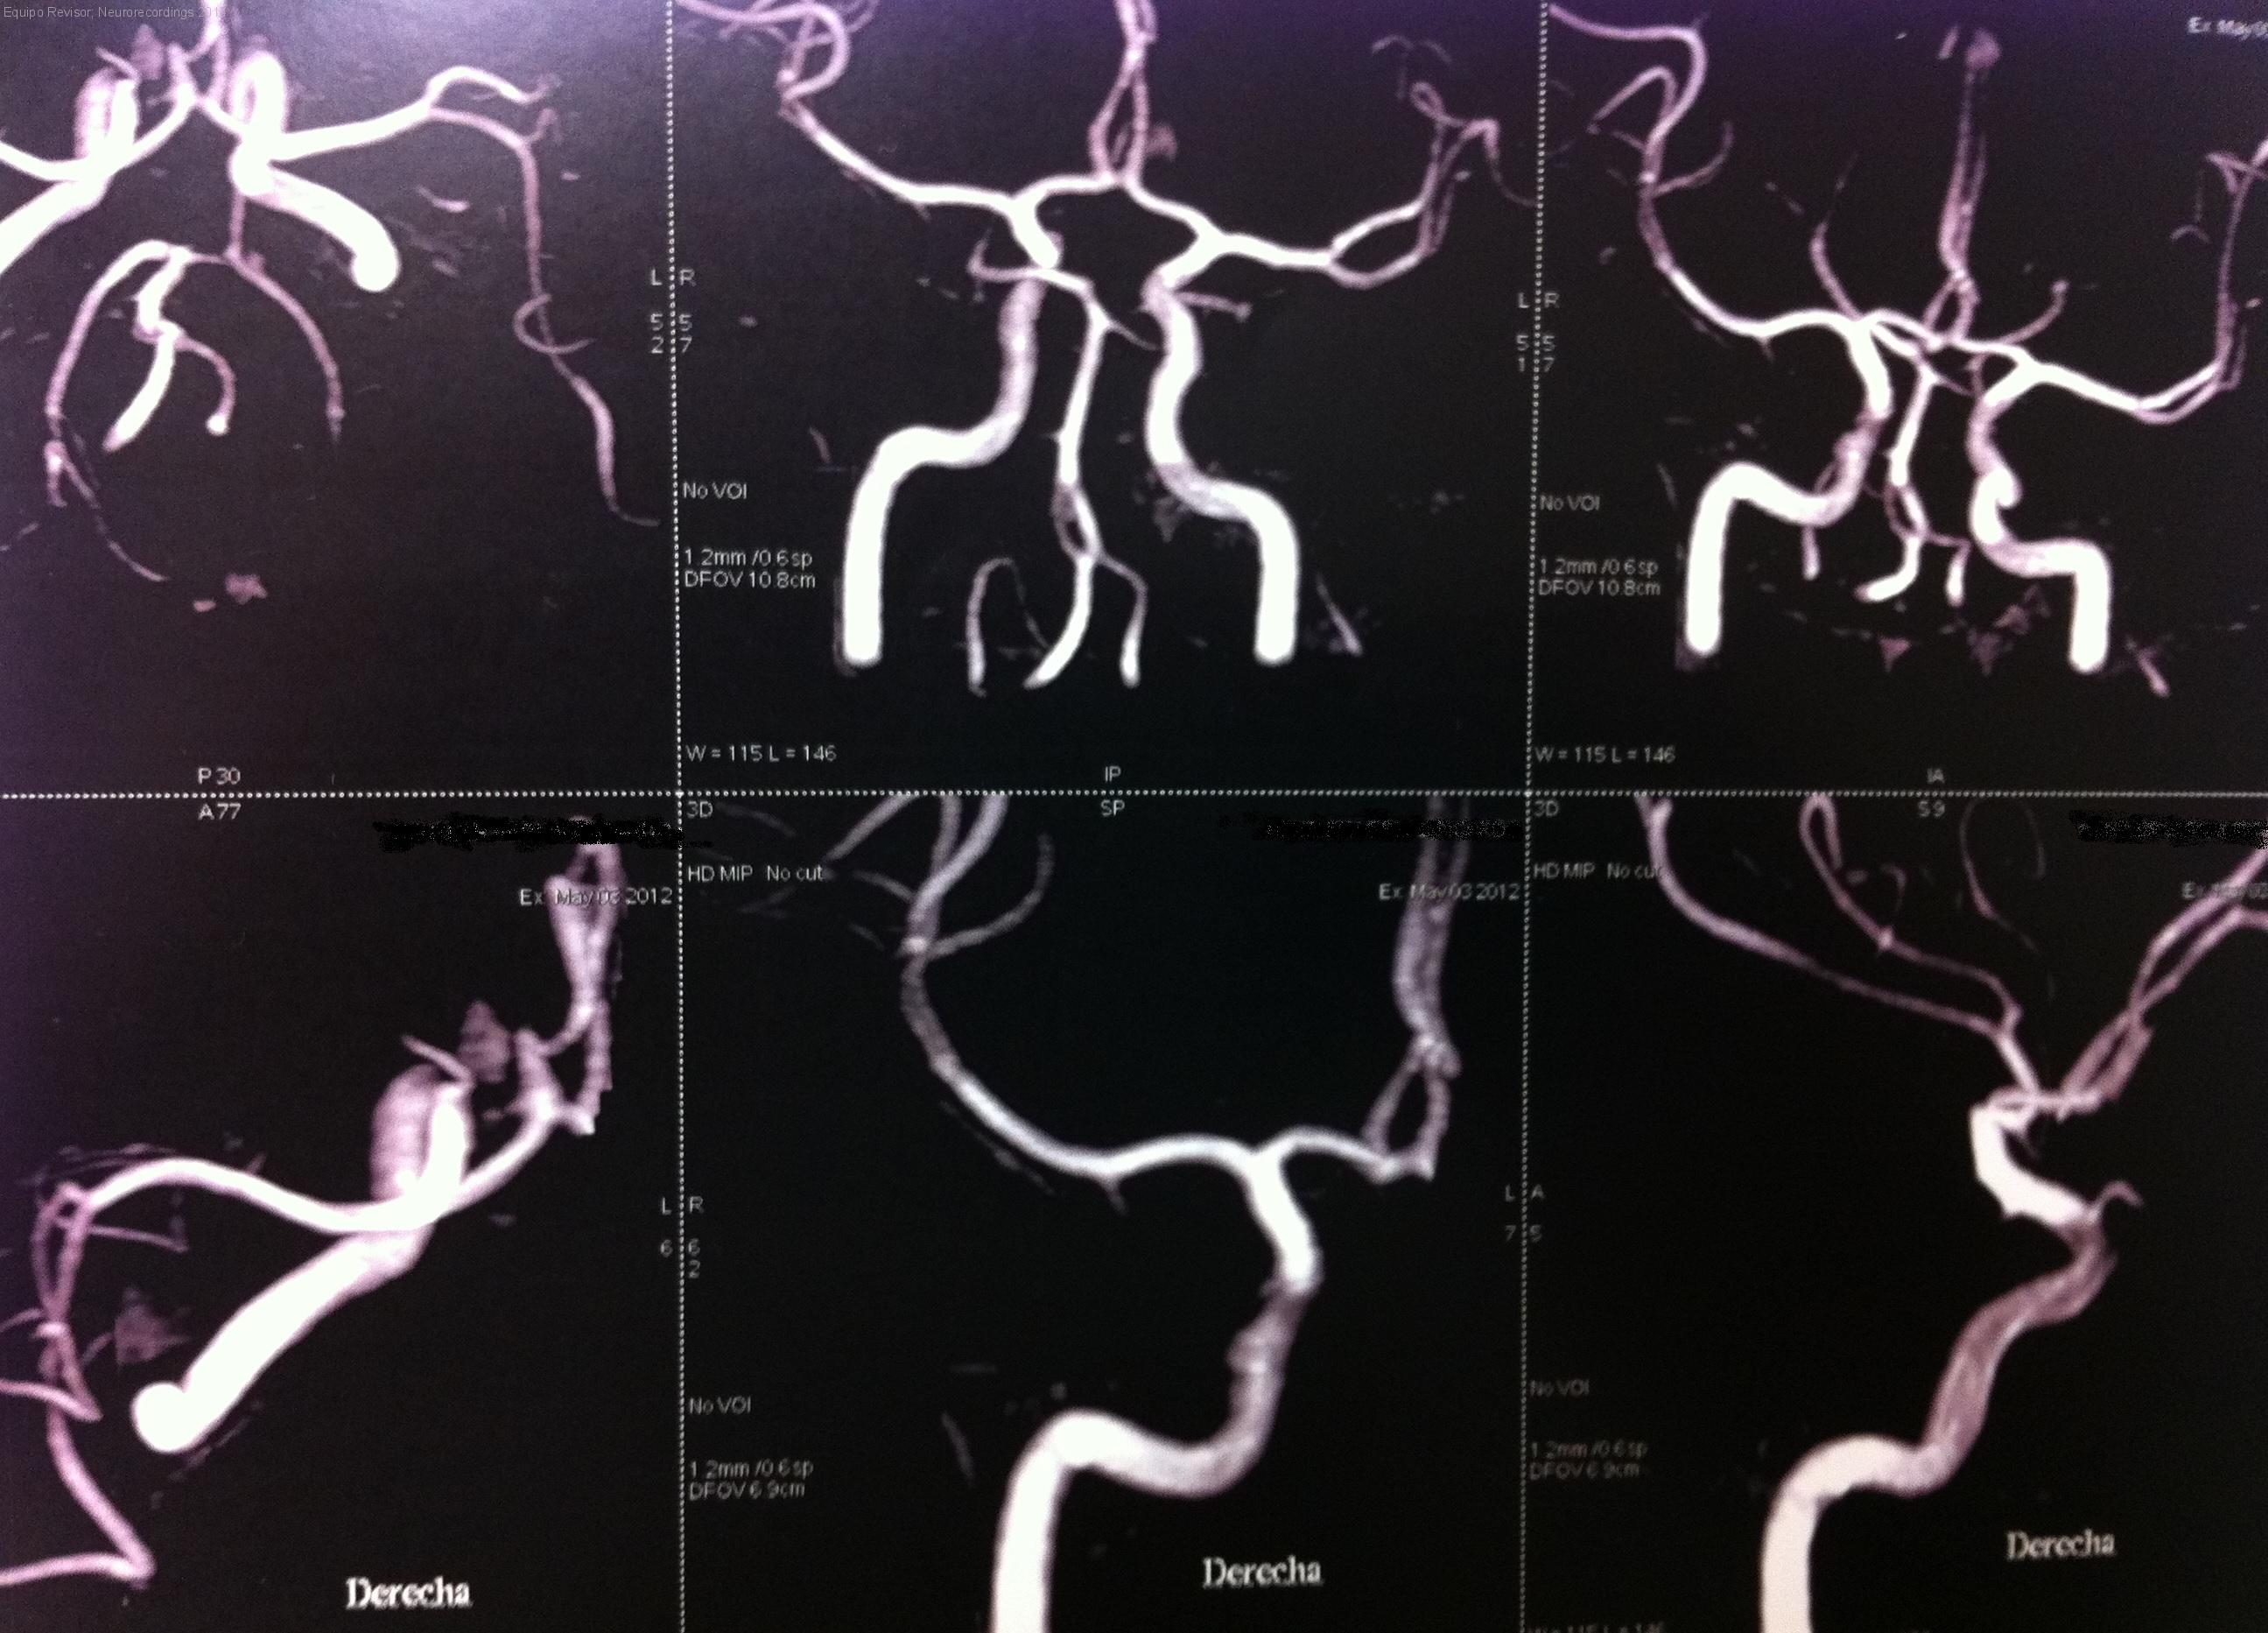

Paciente que presenta cuadros presincopales de repeticion, de perfil neuromediado. Estudio RMN cerebral normal. AngioTC cerebral valorara arteria basilar fenestrada.